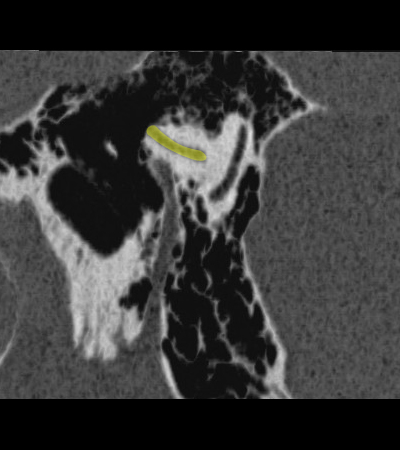

Lateral semicircular canal Posterior semicircular canal Facial nerve (f3), mastoid segment Stylomastoid foramen

Radioanatomy of Temporal bone

Sagittal cut through the mastoid segment of facial nerve. Minimum Intensity Projection reconstruction.